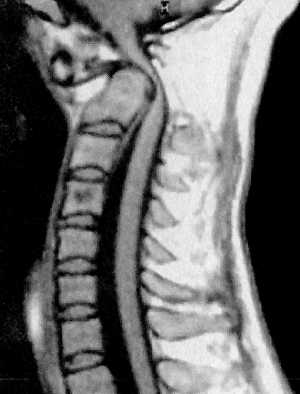

КТ и цифровая спондилография - важные методы диагностики вывихов атланта (рис.

1.7 и 1.8). МРТ позволяет определить не только дислокацию атланта, но и степень

компрессии спинного мозга (рис. 1.9).